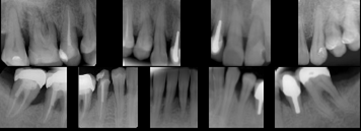

Periometr - první plně automatizovaný přístroj pro zjištění periodontálního statusu pacienta - diagnózy, léčby a profylaxe parodontitidy a dalších onemocnění. Díky správnému určení periodontálnímu statusu pacienta lze včas odhalit a minimalizovat objevující se obtíže.